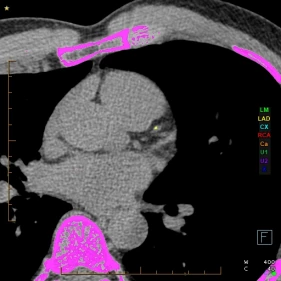

A CT Calcium Score is a quick, non-invasive scan that measures the amount of calcium buildup in your heart’s arteries. This calcium is a sign of atherosclerosis, or hardening of the arteries, which increases your risk of a heart attack.

A CT Calcium Score scan is simple, fast, and does not require any injections or contrast. You will lie on a scanning table, and a low-dose CT scanner will take images of your heart in just a few minutes. The results are then analysed by one of our specialists, and a calcium score is provided. We may also provide you with an adjusted risk of a coronary event.

Your calcium score helps determine your level of risk:

• 0             Very low risk (no coronary calcium)

• 1 - 100       Low risk (mild plaque build-up)

• 101 - 400  Moderate risk (significant plaque build-up)

• >400       High risk (requires further assessment and management)

The higher your score, the higher your risk of a heart attack or other heart-related event.